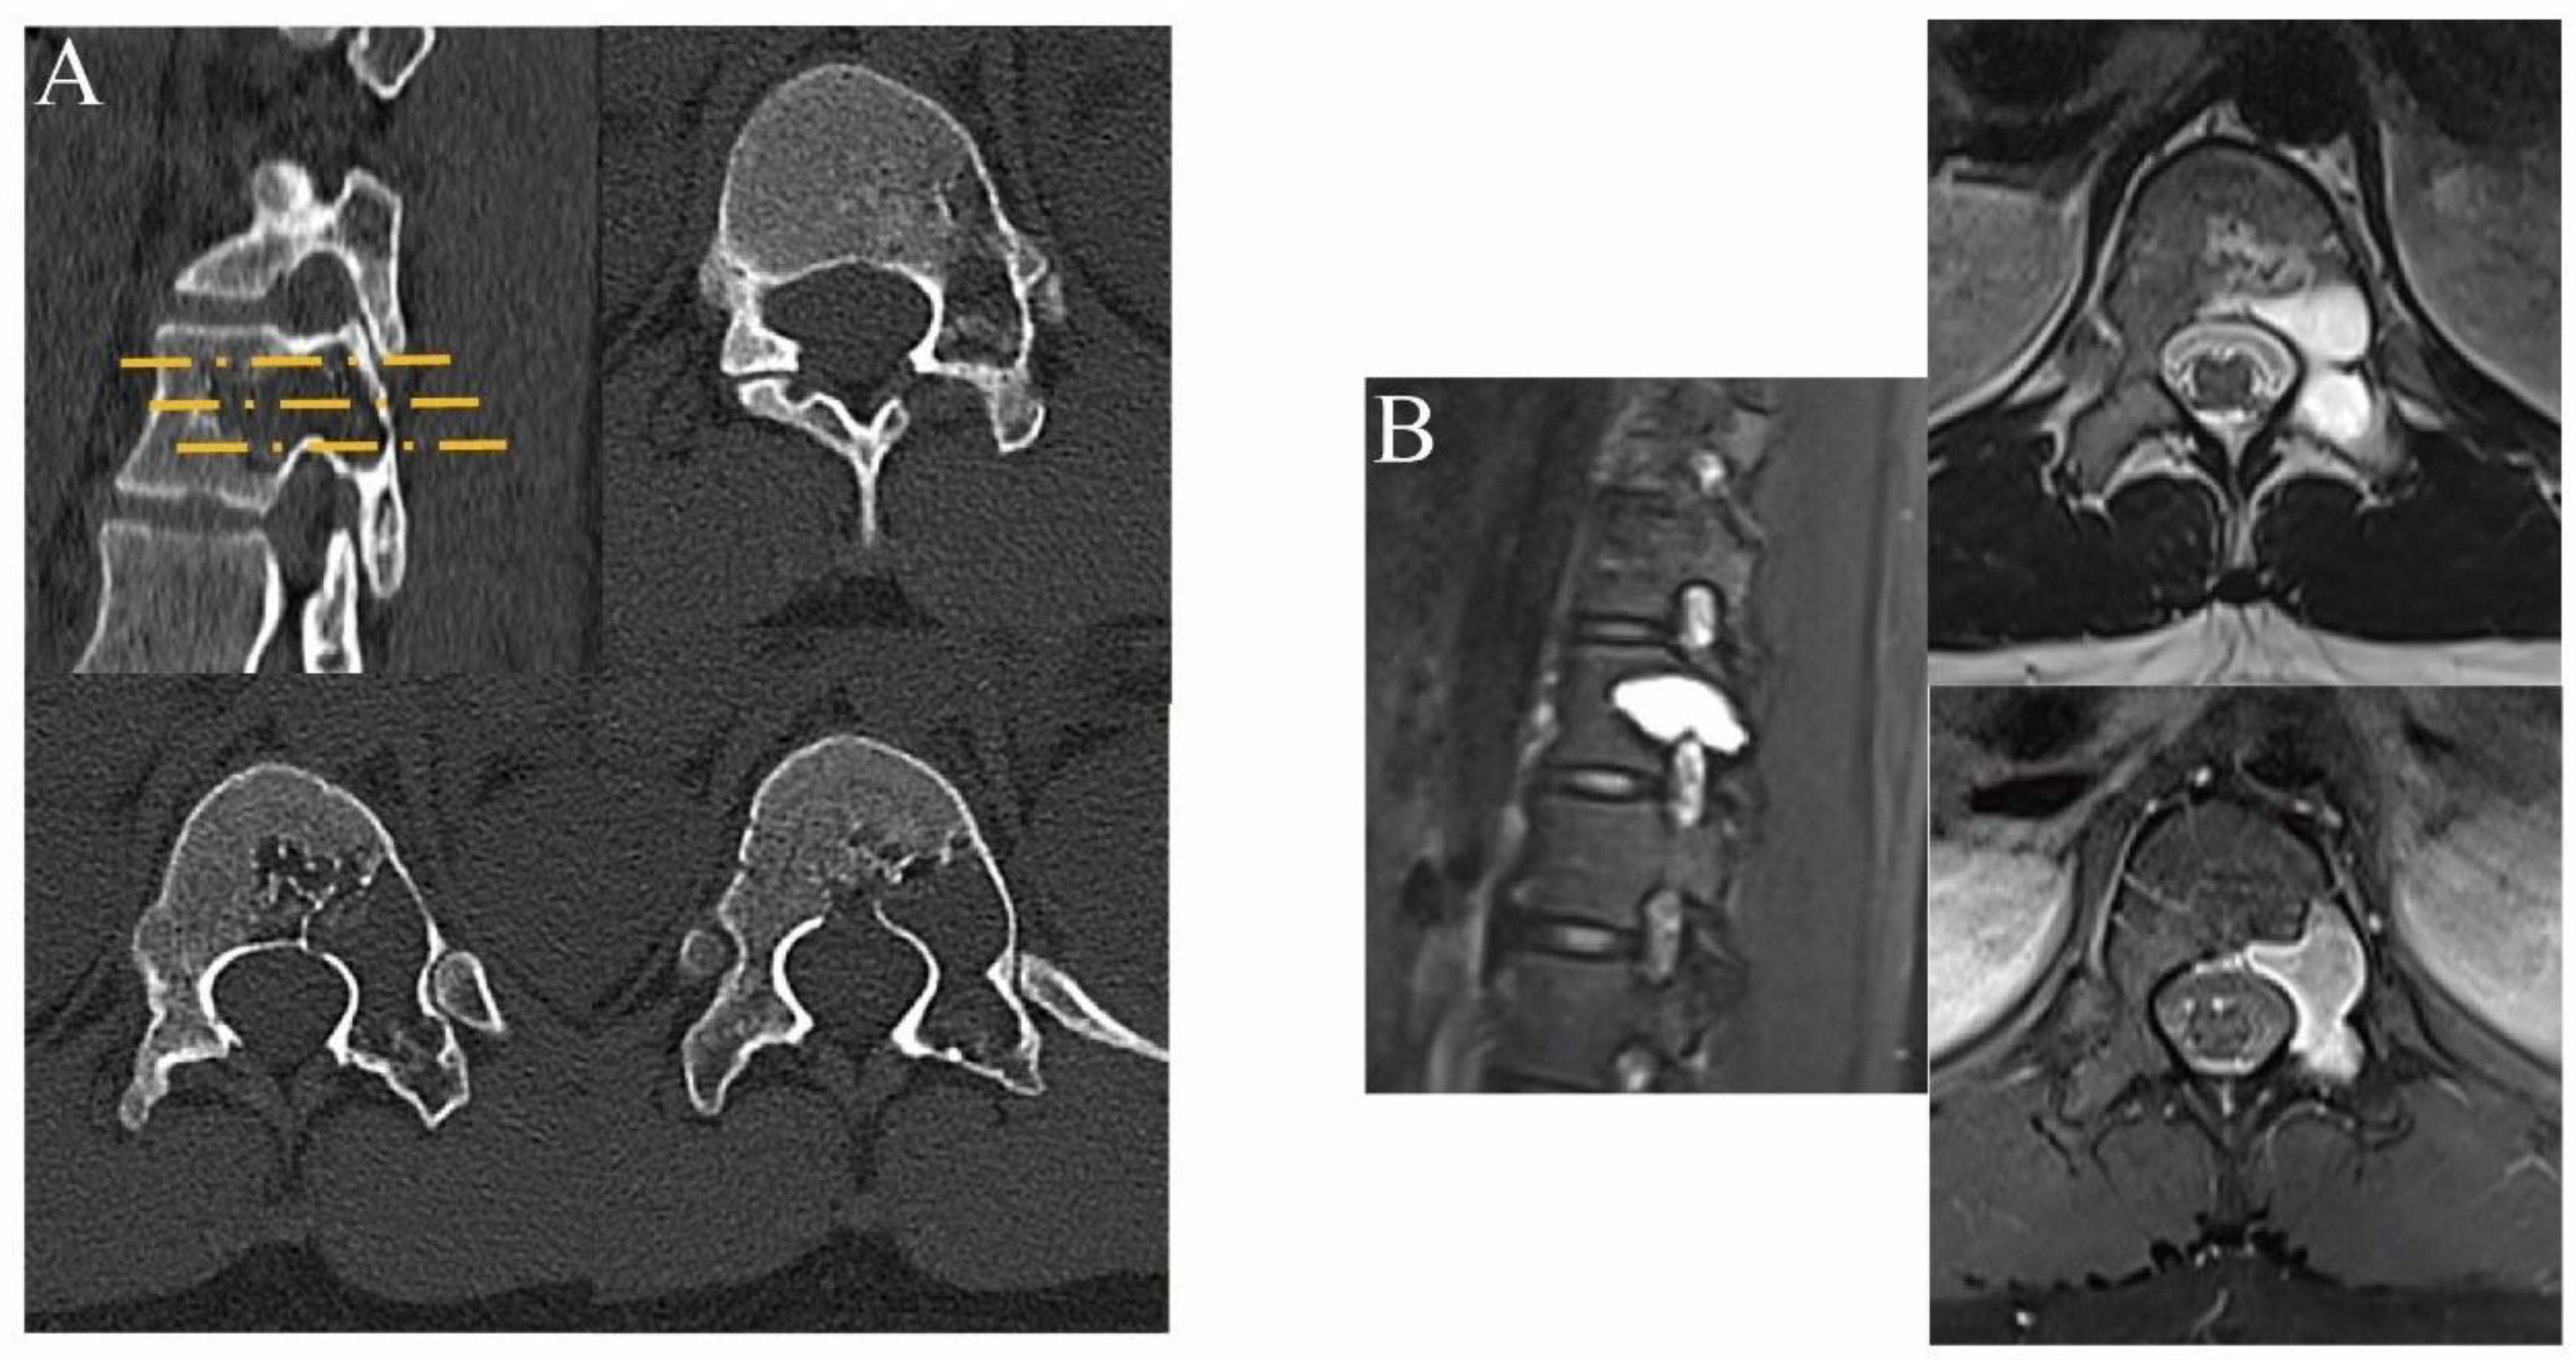

2.1. Preoperative Preparations

2.2. Surgical Technique

2.2.2. Surgical Procedure